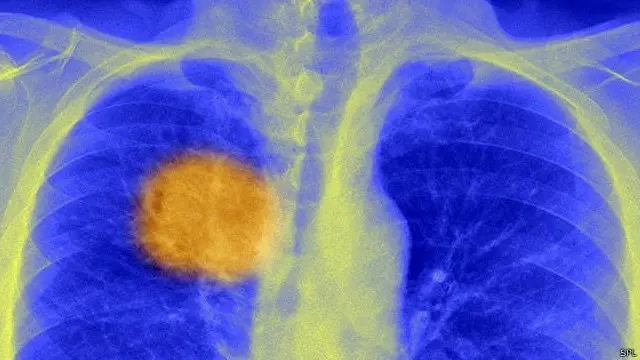

سرطان کا علاج ’نئے عہد‘ میں داخل ہو رہا ہے

ڈاکٹروں کا کہنا ہے کہ سرطان کا علاج انفرادی طب کے ایک ’نئے عہد‘ میں داخل ہو رہا ہے جہاں ہر مریض کو اس کی رسولی کی کسی کمزوری کو ہدف بنانے والی مخصوص ادویات دی جائیں گی۔

سرطان کے خلیے جسم کے عام خلیے ہوتے ہیں جن کے ڈی این اے میں گڑبڑ پیدا ہو جاتی ہے اور وہ قابو سے باہر ہو پھیلنا شروع ہو جاتے ہیں۔ کیموتھیراپی اور ریڈیو تھیراپی سرطانی خلیوں کے ساتھ ساتھ صحت مند خلیوں کو بھی مار ڈالتی ہیں، جن کی وجہ سے شدید مضر اثرات سامنے آتے ہیں۔

تاہم انفرادی علاج کی مدد سے ہر مریض کی رسولی کا تجزیہ کیا جاتا ہے، اس میں وہ مخصوص خرابی تلاش کی جاتی ہے جس کی وجہ سے یہ رسولی بنی اور پھر صرف اسی خرابی کو نشانہ بنانے والی ادویات دی جاتی ہیں جو رسولی کو تباہ کر دیتی ہیں۔